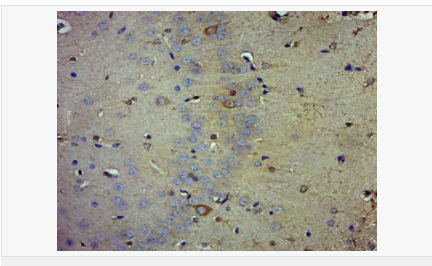

| 產(chǎn)品應(yīng)用 | WB=1:500-2000 ELISA=1:5000-10000 IHC-P=1:100-500 IHC-F=1:100-500 Flow-Cyt=1μg/Test ICC=1:100 IF=1:100-500 (石蠟切片需做抗原修復(fù)) not yet tested in other applications. optimal dilutions/concentrations should be determined by the end user. |

| 細胞定位 | 細胞核 細胞漿 |